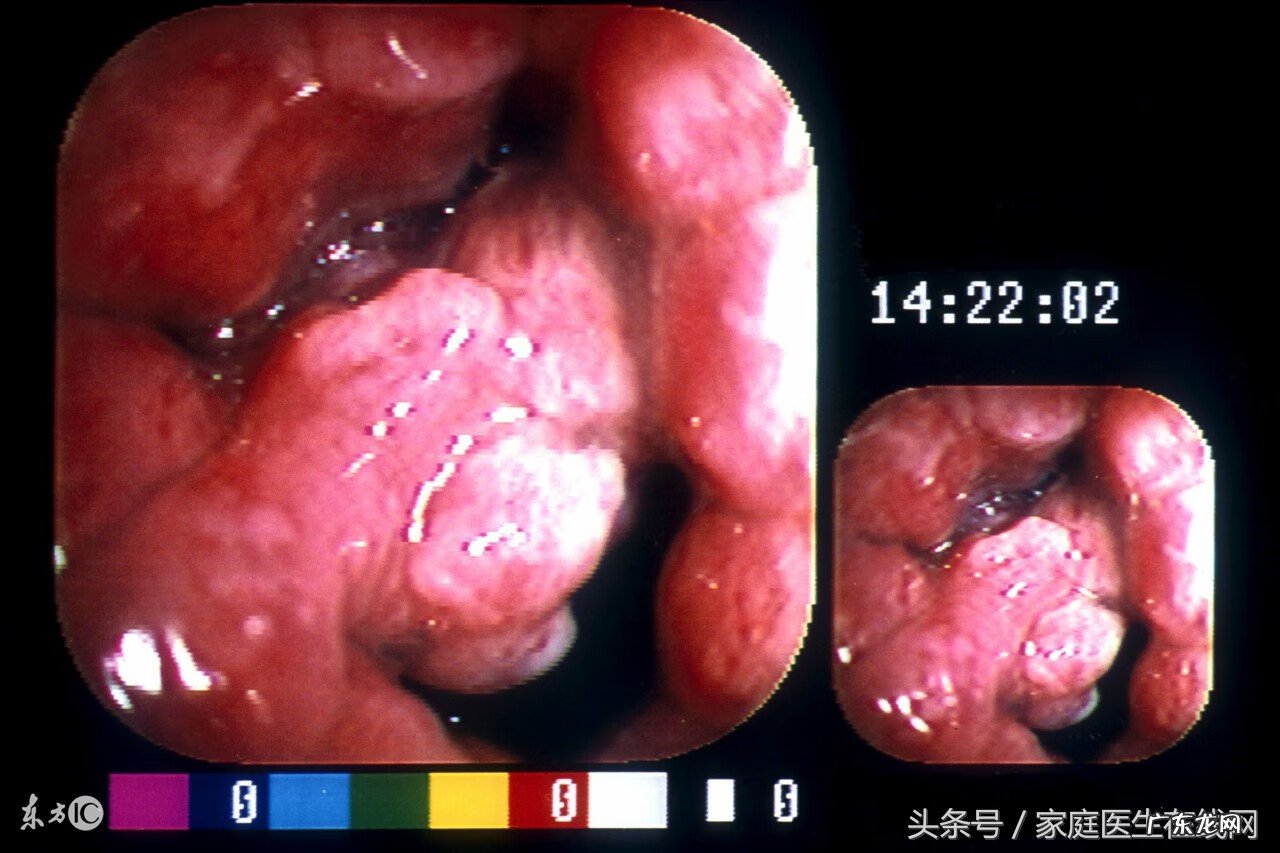

胃癌是一种危害人类健康的重要疾病 。在全球范围内 , 大部分的胃癌患者都集中在中国 , 因此中国也是胃癌的大国 。那么 , 胃癌早期有哪些征兆呢?

胃癌有早期有哪些症状?广州中医药大学第一附属医院肿瘤科林丽珠教授在接受家庭医生在线采访时表示 , 早期胃癌70%以上没有任何症状 , 即便有症状者也通常不典型 , 上腹部轻度不适是最常见的初发症状 , 与消化不良或胃炎相似 , 非常容易忽视 。